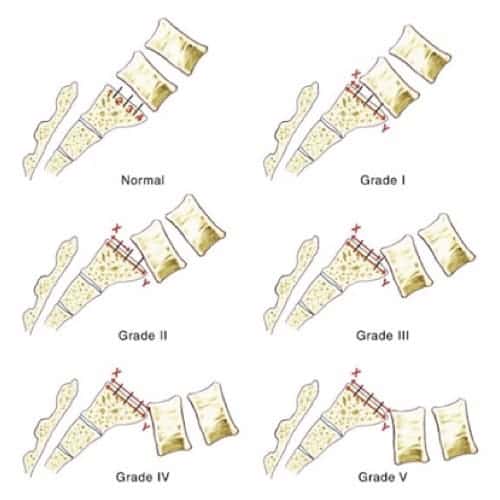

Spondylolyse et spondylolisthésis isthmique sont des aspects différents d’une affection dont la variabilité clinique est remarquable. Quantification du glissement. Clinique. Spondylolyse isthmique. Clinique. Imagerie. Formes cliniques. Indications thérapeutiques. Techniques chirurgicales.. La lyse se située plus souvent à l’étage L5/S1 mais peut parfois se retrouver à l’étage L4/L5. il est habituel que classer le glissement, occasionné par la lyse, en 4 stades de Meyerding. TRAITEMENT. Avant tout il est médical avec des antalgiques, de la rééducation associée au besoin à des infiltrations.

Le spondylolisthésis implique habituellement les vertèbres L3-L4, L4-L5 ou le plus souvent L5-S1. Les types II (isthmique) et III (dégénératif) sont les plus fréquents.. Dans la majorité des cas, le spondylolisthésis concerne les vertèbres les plus basses, surtout au niveau de la jonction entre la colonne lombaire et le début de la colonne sacrée. La localisation entre la 4e et la 5e vertèbre lombaire est la plus commune : on parle de spondylolisthésis L4-L5.